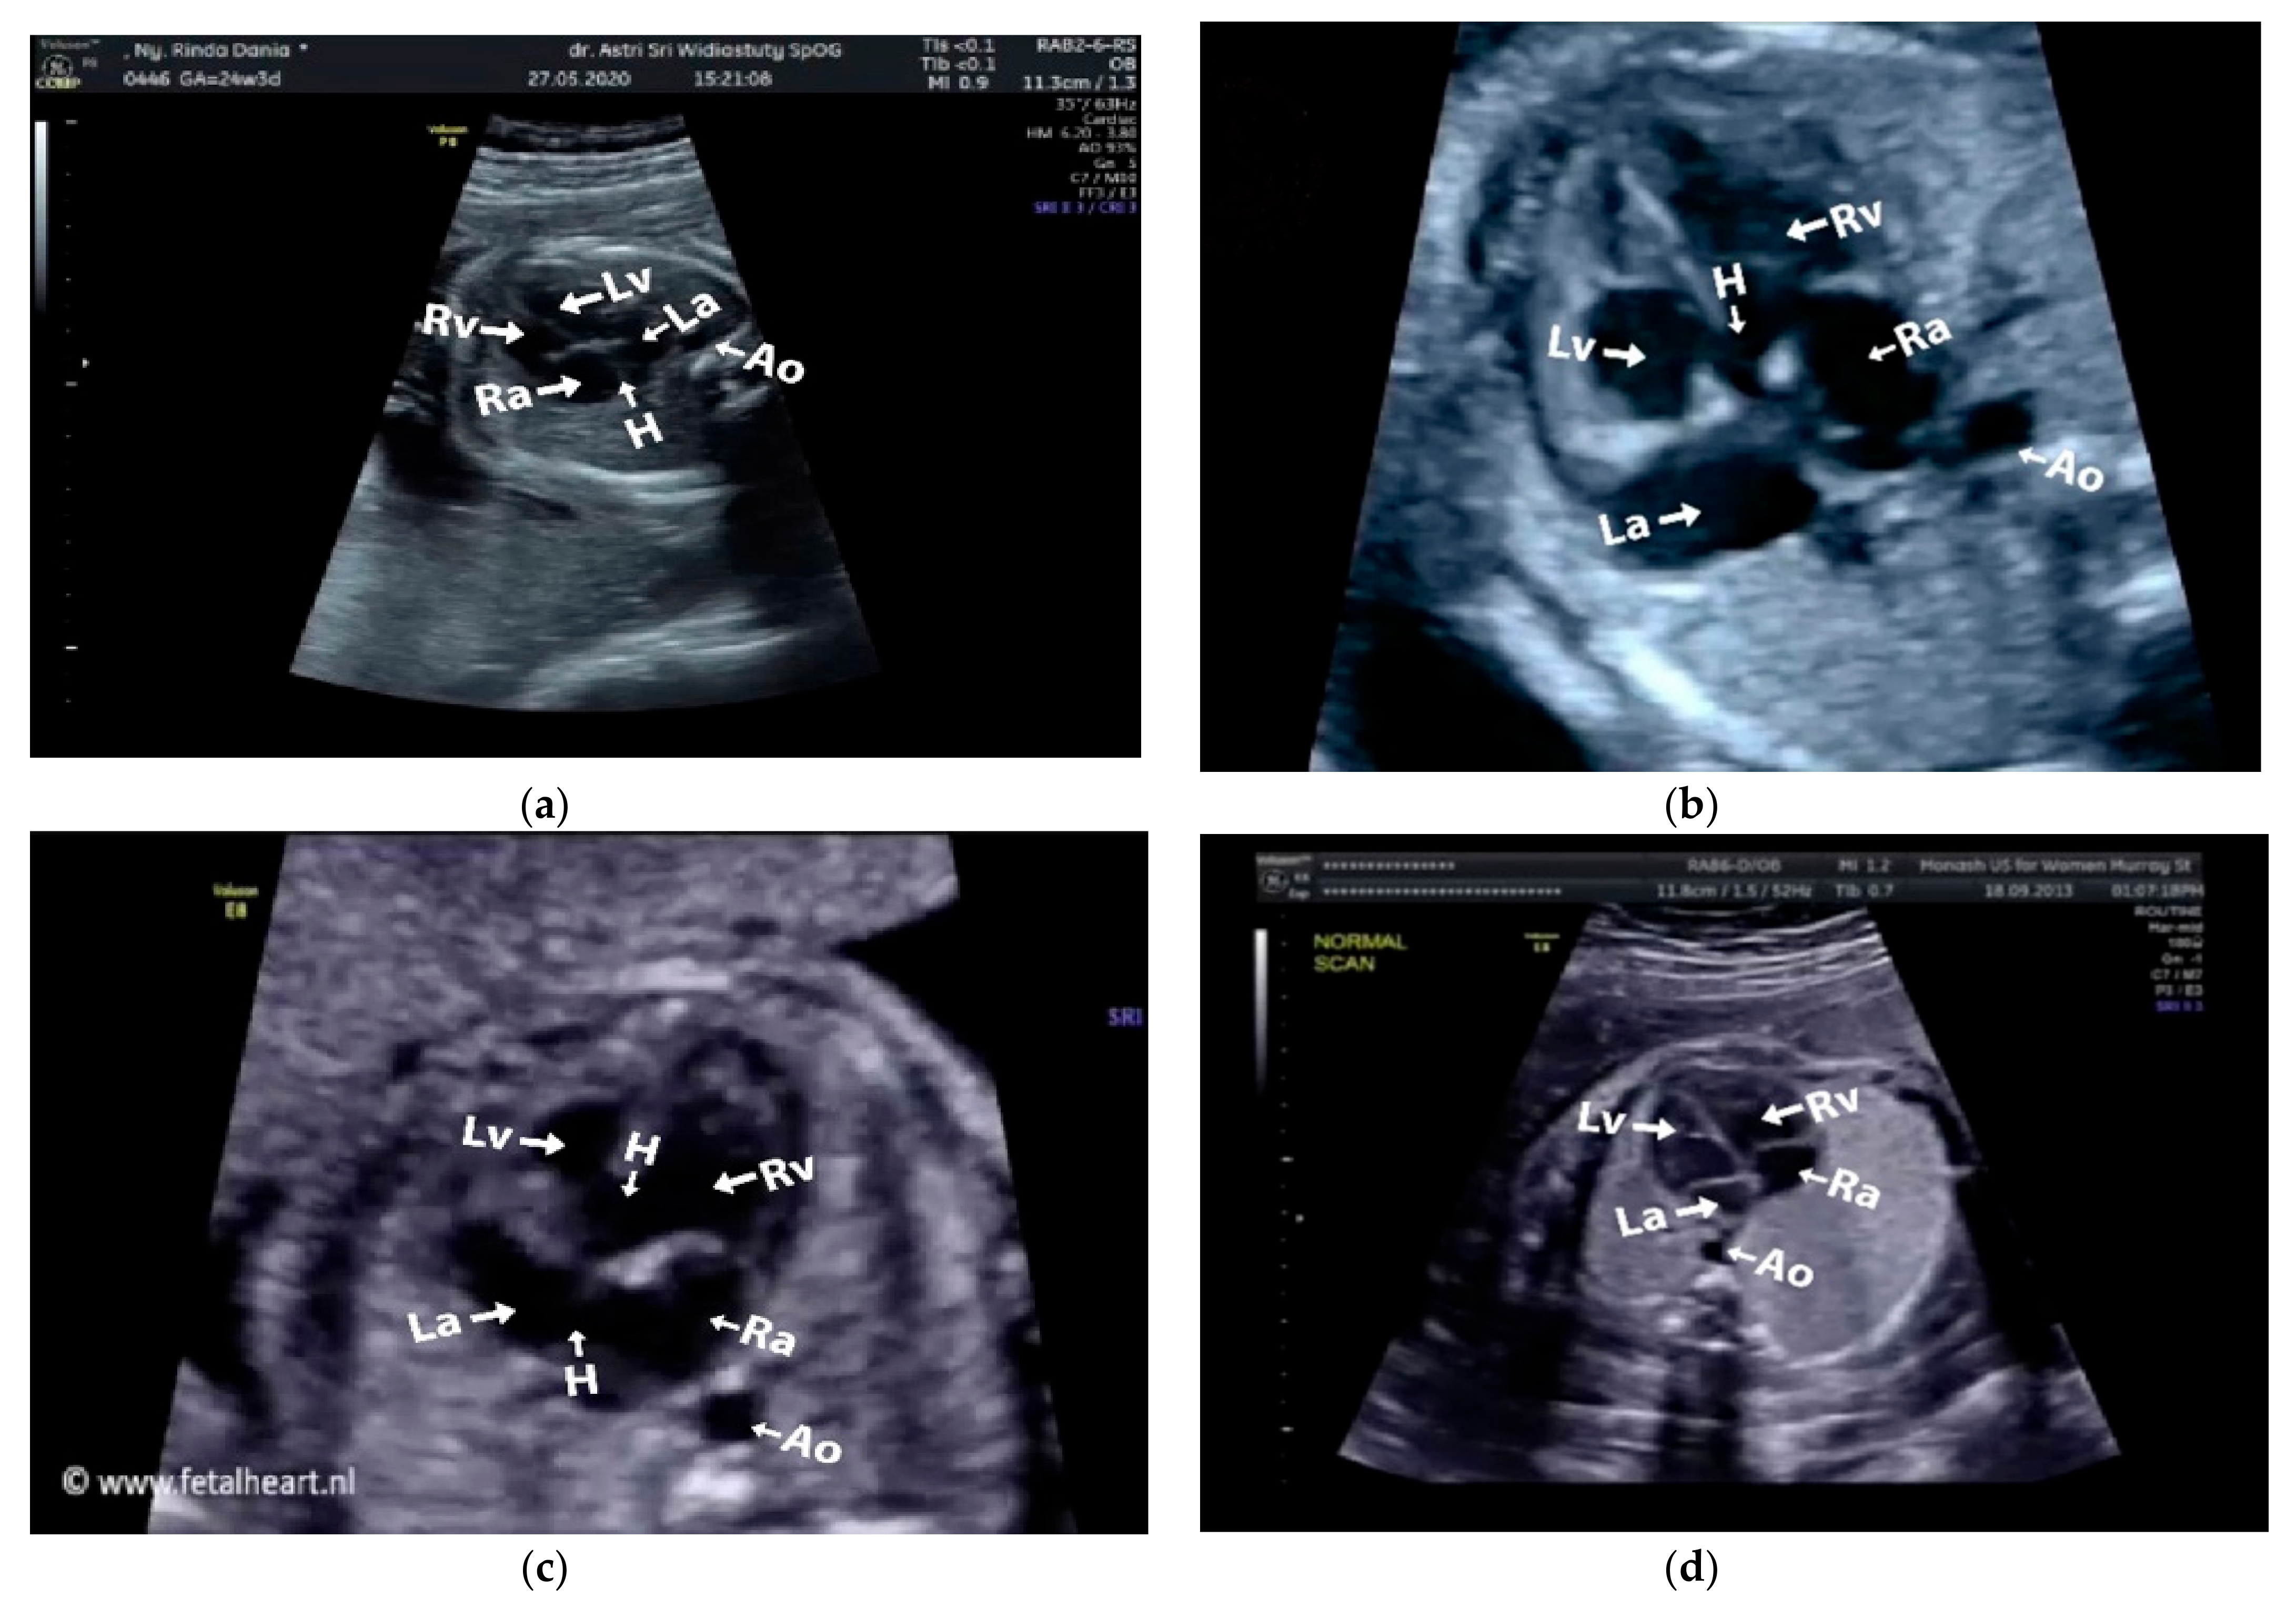

Images with inappropriate anatomical planes (cropped or badly captured) and those with calipers were excluded. The dataset composition was clearly imbalanced (some classes were more frequent than others), as is usually the case in real clinical scenarios. The sample of the raw ultrasound image was based on four views in normal anatomy, as depicted in Figure 2. In such sample, there are the left atrium (LA), left ventricle (LV), right atrium (RA), right ventricle (RV), ductus arteriosus (DUCT), superior vena cava (SVC), aorta ascendens (AoA), aorta descendens (Ao), and main pulmonary artery (MPA), whereas the sample of the raw ultrasound image of abnormal anatomy structure, with the three heart defects such as ASD, VSD, and AVSD condition, is compared to normal anatomy structure in Figure 3. In the abnormal structure, there are hole (H) as heart defect in each condition. Each defect has the variation of hole size; such hole size indicates the disease severity. However, in this study, we only detected the hole, without measuring the hole size.

Figure 3.

Fetal heart scan in 4CH view for CHDs detection: (a) ASD; (b) VSD; (c) AVSD; and (d) Normal.